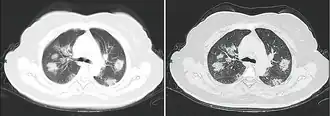

КТ грудной клетки иногда может помочь идентифицировать и охарактеризовать патологию лёгких и дать неспецифические результаты при инфекции COVID-19. Систематический обзор результатов компьютерной томографии грудной клетки у 919 пациентов описал типичное раннее проявление COVID-19 как «двустороннее мультилобарное помутнение матового стекла (GGO) с периферическим или задним распределением».[19] Одно исследование показало, что чувствительность КТ к инфекции COVID-19 составила 98 % по сравнению с чувствительностью ОТ-ПЦР на 71 %; однако это было сделано в китайской провинции Ухань и не подлежит обобщению.[20] Наиболее распространёнными результатами компьютерной томографии были двустороннее затухание матового стекла (пятнистое или рассеянное) с субплевральным доминированием, сумасшедшей укладкой и консолидацией на более поздних стадиях.[21] Эти данные являются неспецифичными и обнаруживаются также при других типах пневмонии. Небольшое исследование показало, что китайские рентгенологи продемонстрировали чувствительность 72-94 % и 24-94 % в дифференцировании COVID-19 от других типов вирусной пневмонии с использованием компьютерной томографии.[22] Ни одно исследование ещё не подтвердило точность и дискриминационную ценность компьютерных томографий, чтобы отличить COVID-19 от других вирусных пневмоний. Поэтому CDC не рекомендует КТ для первоначального скрининга, как подчёркивалось в звонке COCA в четверг, 5 марта. Люди с подозрением на COVID-19 должны проходить ОТ-ПЦР, которая является наиболее специфическим тестом.[23]

Типичные результаты компьютерной томографии